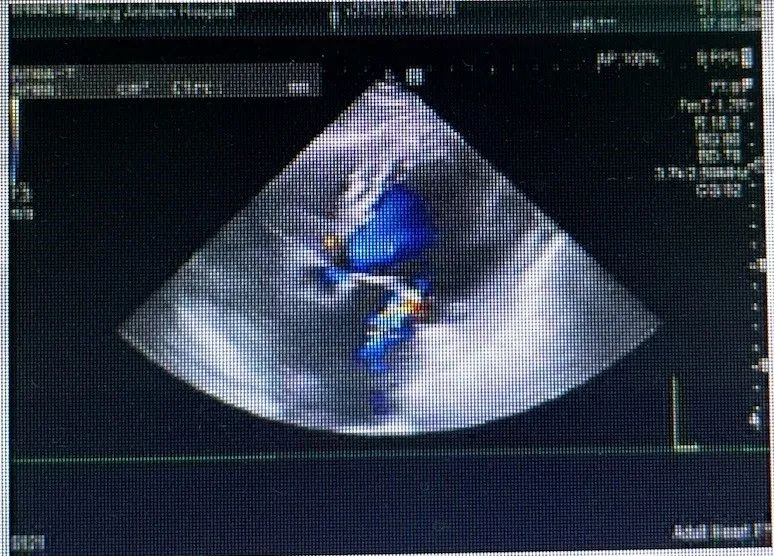

心脏彩超

舒张期主动脉瓣下见大量反流信号

缩流颈8mm

左室射血分数EF值: 40%

左室舒张末期内径(LVD):66 cm

主动脉瓣评估:左心增大,左心功能减低,二尖瓣反流(重度)、三尖瓣反流(轻度),肺动脉高压(轻度)并少许心包积液